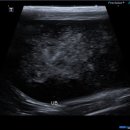

환자들의 후기 등을 미리 살펴보는 것이 도움이 될 수 있습니다. ​ 다음으로, 병원의 시설과 장비 역시 중요한 고려 사항입니다. 최신 진단 장비(예: X-ray, 초음파, 혈액 검사 장비)를 갖추고 있는지, 수술실이나 입원실의 위생 상태는 어떠한지 등을 확인해야 합니다. 특히 응급 상황 발생 시 신속하고 정확한 진단과...

• 선부중앙동물의료센터 | 강아지 요로 결석 재발 재수술 후기

​ ​ ​ 강아지 결석 재발 재수술 후기 강아지 요로결석, 방광결석 재발로 재수술하게 된 후기 남겨봅니다. 반려견 결석은 재발률이 높은 편이라고 해서 꾸준히 관리...이번 수술은 선부중앙동물의료센터에서 진행했어요. ​ ​ ​ ​ 📍선부중앙동물의료센터 정보 주소 : 경기 안산시 단원구 선부광장1로 69 단지내상가동 2층...